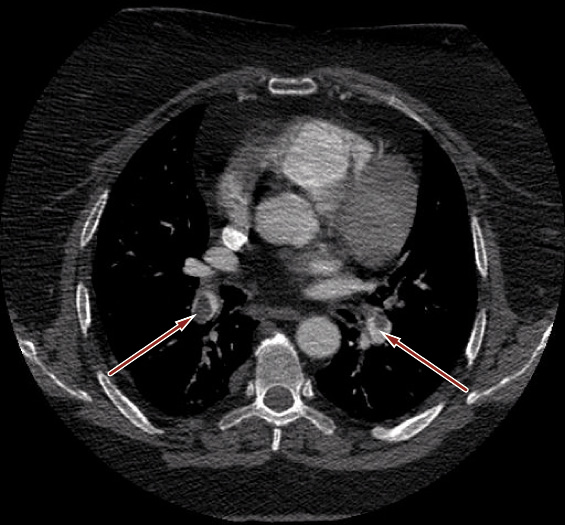

L’angio-Tc polmonare dimostra multipli difetti di riempimento endoluminale di tipo trombotico nel ramo sinistro dell’arteria polmonare e nelle diramazioni segmentarie e subsegmentarie bilateralmente, qualche area di consolidamento parenchimale alle basi a sede subpleurica, esilissimo versamento pleurico a destra (Figura 2).

Figura 2. AngioTc polmonare